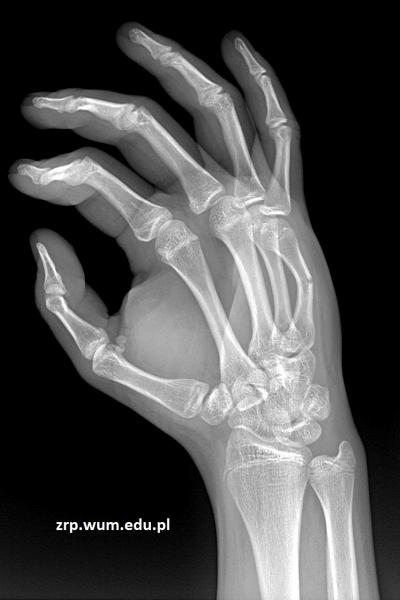

16-latek po urazie śródręcza prawego

Przypadek 61: 16-latek po urazie śródręcza prawego - przypadkowe uderzenie w słup.

Rozpoznanie: Złamanie środkowej części trzonu 5-ej kości śródręcza, z ugięciem odłamu dystalnego.